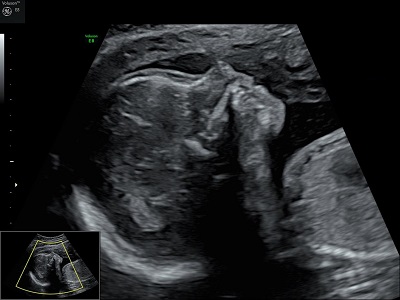

"Voir ce qui est invisible, grâce à des sons inaudibles."

En tant que profession médicale, nous pouvons pratiquer toutes les échographies de dépistage au cours de la grossesse, ainsi que les échographies pelviennes (gynécologiques), après l'obtention d'un diplôme inter-universitaire d'échographie obstétricale et gynécologique.

Nous utilisons pour réaliser nos examens un échographe performant, le Voluson E8 de chez General Electric. Ainsi, il n'est plus nécessaire de boire beaucoup d'eau avant une échographie.

Nous réalisons les 3 échographies obstétricales recommandées pour le suivi de la grossesse.

échographie T1